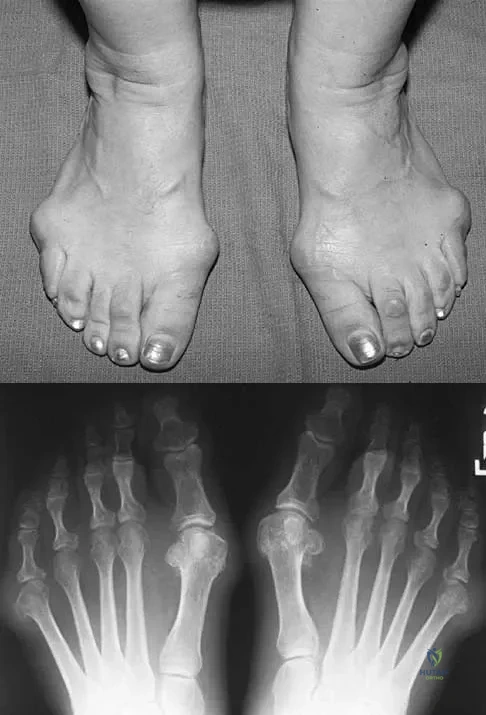

An active 47-year-old woman with rheumatoid arthritis reports forefoot pain and deformity and has difficulty with shoe wear. Examination reveals hallux valgus and claw toes. A radiograph is shown in Figure 10. What is the most appropriate surgical treatment?

Explanation